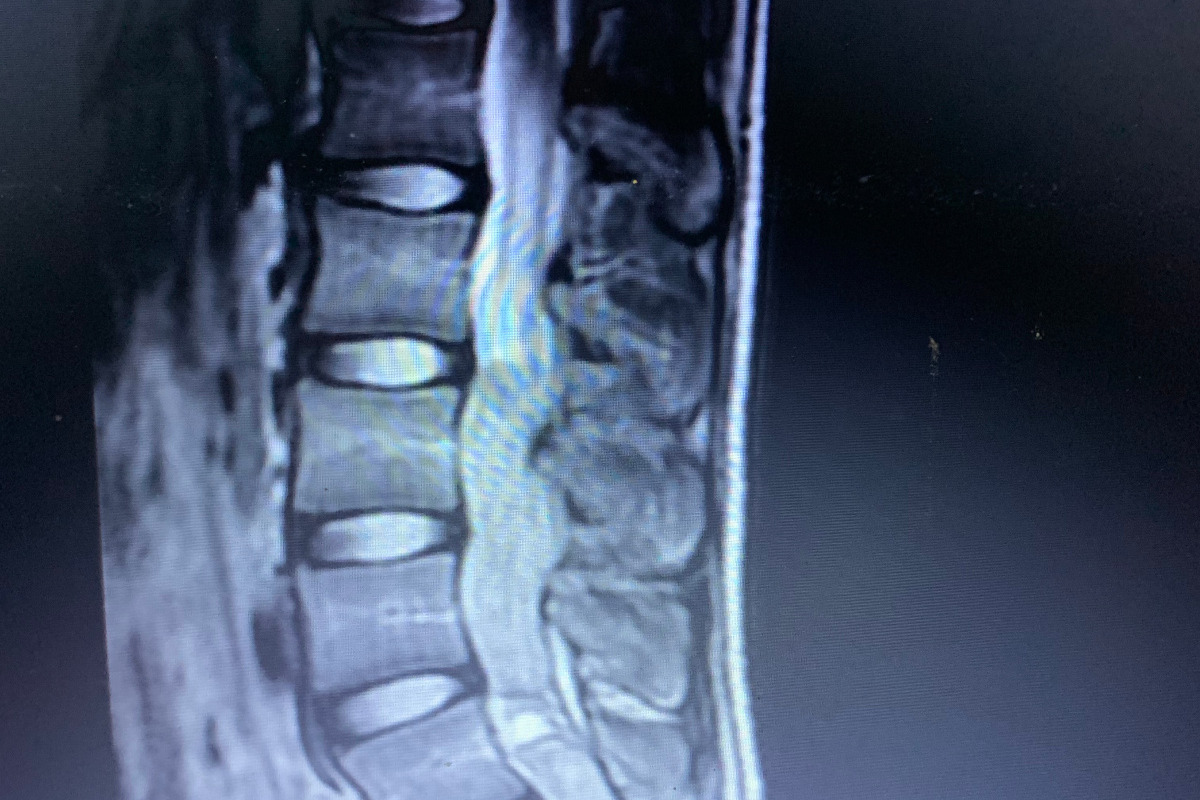

At the specialist they learned that Miguelito has an intradural extramedullary spinal tumor.  His tumor is growing on the spine, compressing his spinal cord and nerves. In order for Miguelito to potentially return to a normal life he needs to have surgery, and he needs to have it fast. This type of tumor grows rapidly, and the doctor informed the family that if he does not complete Miguelito's surgery by the end of July, the tumor will have grown to a new point, making it more complicated and more costly. If not treated, Miguelito's spinal cord and nerves will continue to be compressed by the tumor.